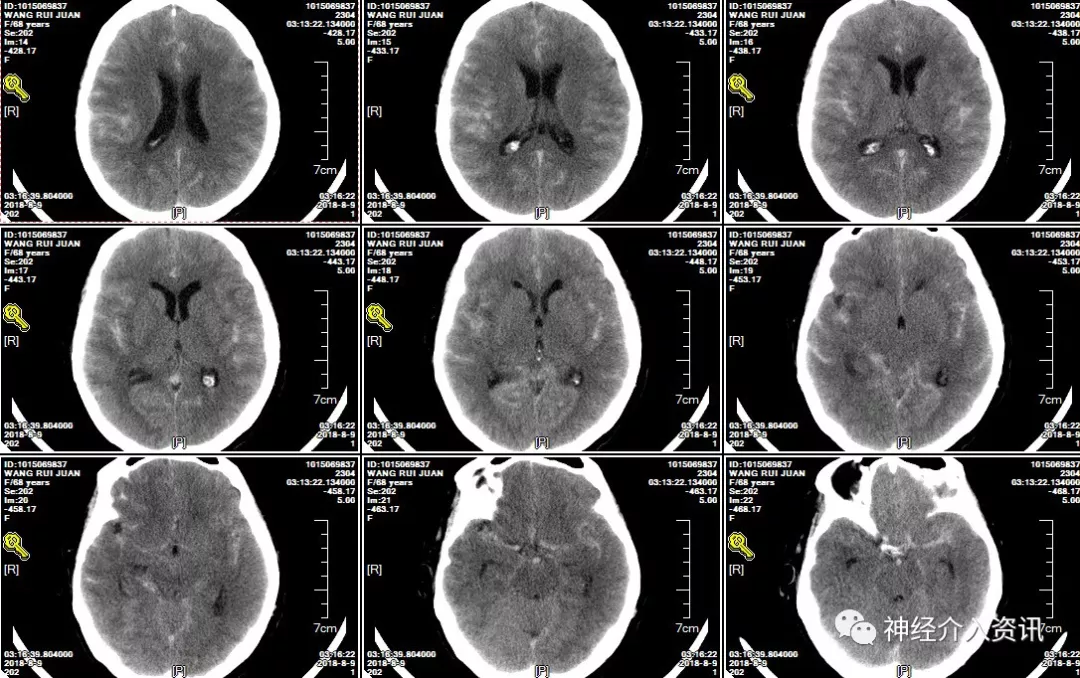

患者以“劳累后突发昏迷12小时”为主诉入院,入院查体颈强直,脑膜刺激征阳性,余神经系统查体无异常。头部CTA提示蛛网膜下腔出血,右侧大脑中动脉动脉瘤。完善术前准备后,于次日行全脑血管造影术,造影见右侧大脑中动脉动脉瘤,M1M2分叉处动脉瘤,2.8*2.5mm,瘤颈3.0mm;另一处脉络膜前动脉动脉瘤,1.5*1.0mm,瘤颈1.5mm。计划同时处理两处动脉瘤。

图一 入院CT广泛蛛网膜下腔出血